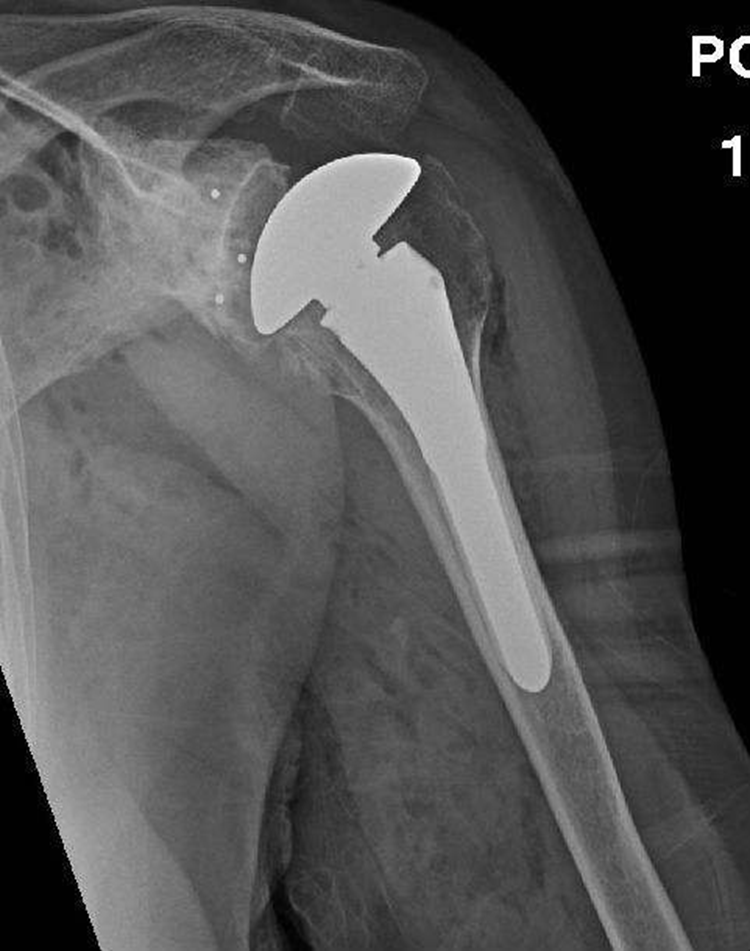

我院骨伤科在常规开展髋关节、膝关节置换手术的基础上,于近日顺利完成一例肩关节置换手术。该手术的常规开展,标志着我院骨伤科在骨关节手术上又实现了一个新的突破。

据了解,该患者已经八十多岁的高龄,因左肩关节粉碎性骨折、活动受限入住我院。骨伤科医务人员为其进行了相关检查,诊断为左肱骨近端粉碎性骨折,如果保守治疗或切开复位内固定手术效果差,如果按传统采取内固定手术,患者术后存在骨折不愈合及肱骨头坏死几率较高等问题,且肩关节功能恢复较差,经骨伤科医疗团队研究后决定采取肩关节置换术。在经过充分的术前准备,制定了完善的手术方案后,在多学科的通力合作下,手术取得了圆满成功。(投稿/骨伤科 胡高)

随着科技的发展,人工关节置换已成为治疗关节疾患的重要的骨科手术之一。目前人工髋关节置换和人工膝关节置换已在国内大量开展。早在 20 世纪 70 年代,人工肩节置换就已在欧美国家得到广泛地应用,它在治疗肩关节骨性关节炎、类风湿性关节炎及复杂肱骨近端骨折方面有着不可替代的重要地位。通过 30 多年的经验积累,人工肩节置换手术已成为一种极为成熟和可靠的术式。